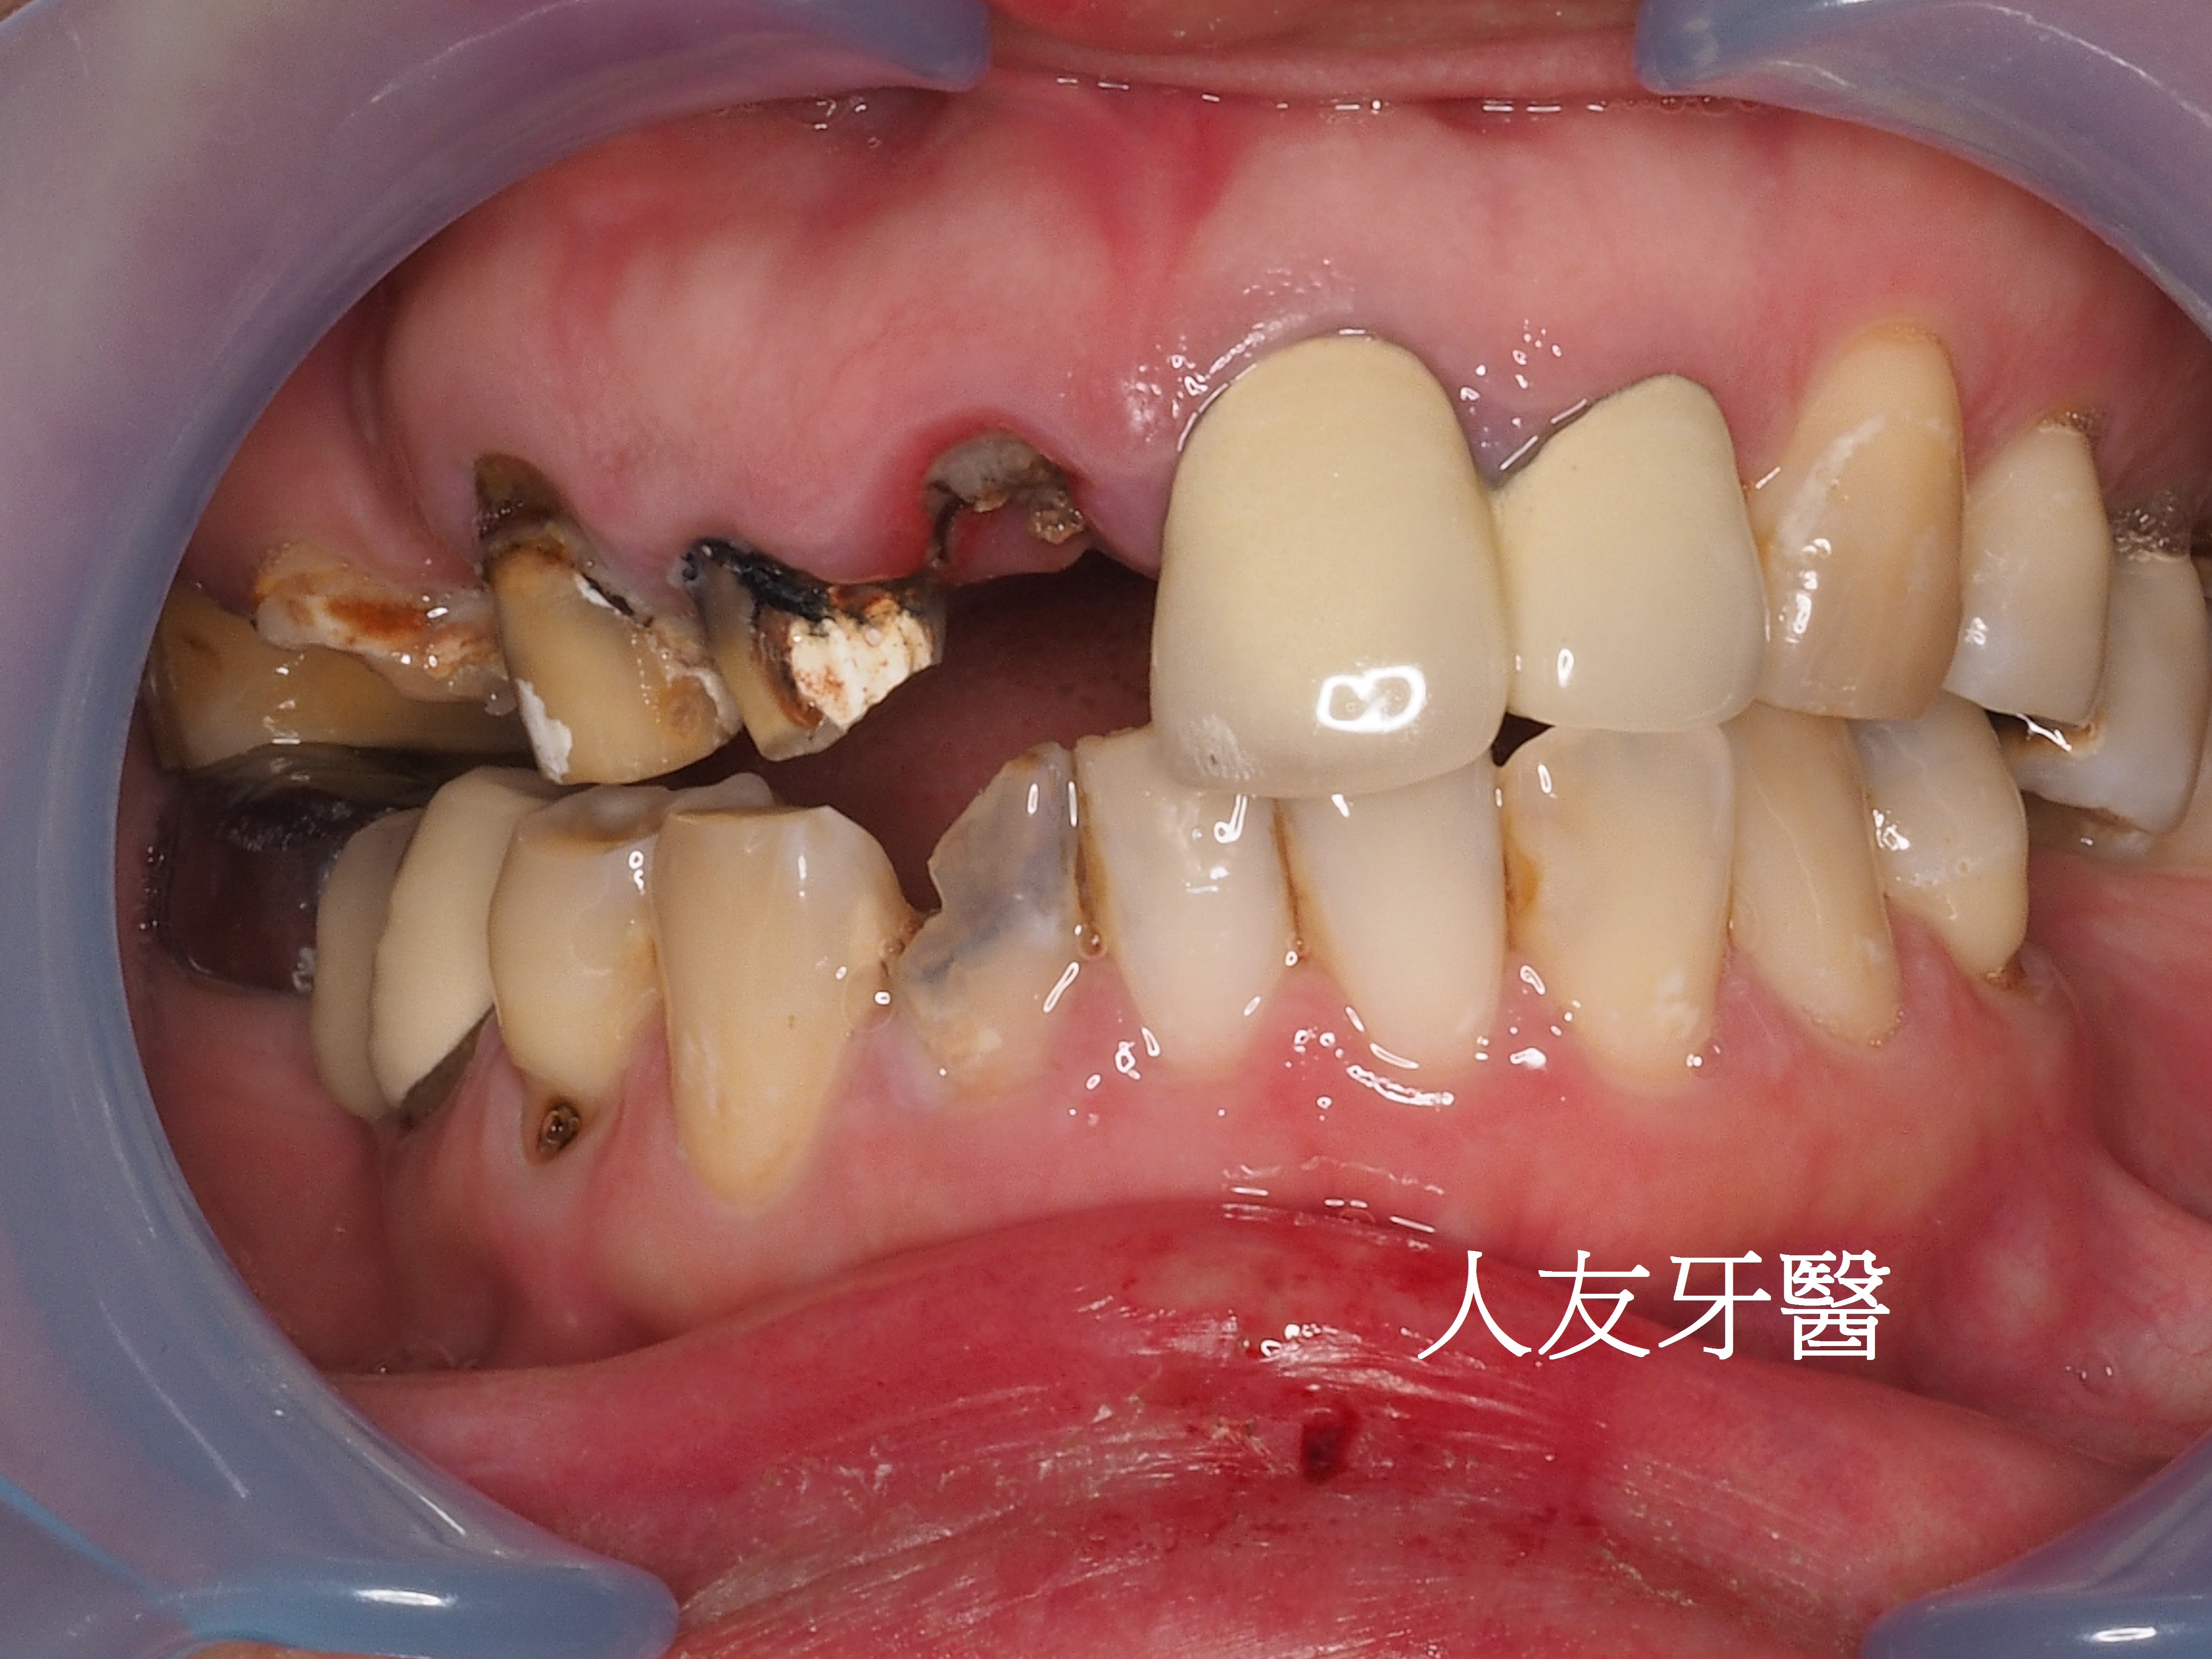

這位年輕女性患者的門牙和側門牙在別家治療半年,也有做四顆相連的牙橋,一直覺得很不舒服,笑起來不自然也不美觀,聽到鑽牙齒的聲音也很害怕。

想詢問周醫師如何處理。醫師看了X-RAY發現右邊側門牙紅色圓圈的地方有病變,有可能留不住。左邊側門牙藍色箭頭牙齒有裂到肉,也可能留不住。經過討論後建議都拔除。

拔完牙後一個月,看傷口癒合情況,因兩顆門牙缺牙太久,齒槽骨流失比較多,醫師建議補骨跟植牙同時進行,植入三根牙根,位置分別在於右邊側門牙一顆,右邊正門牙和左邊側門牙。